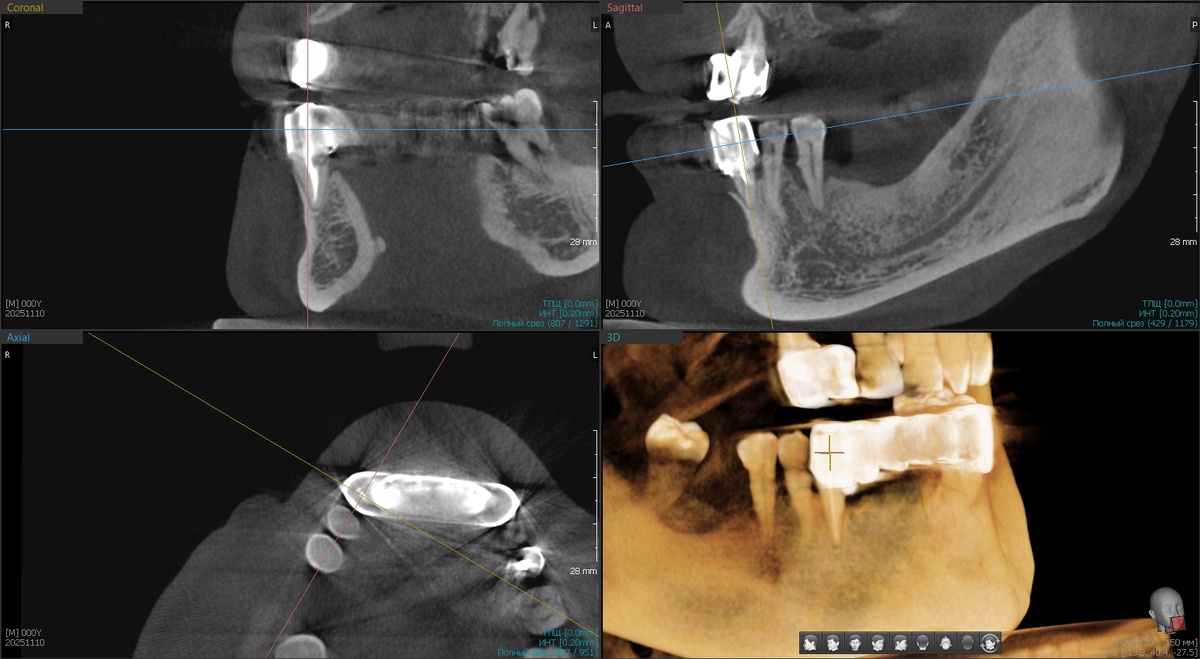

• КТ челюстей в формате DICOM в боьшом формате (должны помещаться суставы и пазухи) - это главное. Файл не старше 6 месяцев. По нему врач оценит объём и качество кости, увидит анатомические особенности, поймёт примерный (но достаточный для понимания тактики) объём работы.

Дистанционная оценка

После получения данных на почту кураторы оперативно передают задачу врачу - он изучает КТ, фотографии и всё остальное. Оценивает состояние костной ткани, положение гайморовых пазух, расположение нижнечелюстного нерва, соотношение челюстей.

В случае нашего пациента ситуация была следующая - нижняя челюсть в критическом состоянии, верхняя под вопросом.

Решено было начать работу с челюстью нижней, а верх под наблюдение - бруксизм, адаптация нужна будет. Ну и, не смотря на неприглядный внешний вид и деструкцию кости, есть вероятность, что зубы на в/ч ещё побудут с человеком. Их вид его не смущает. И это хорошо.